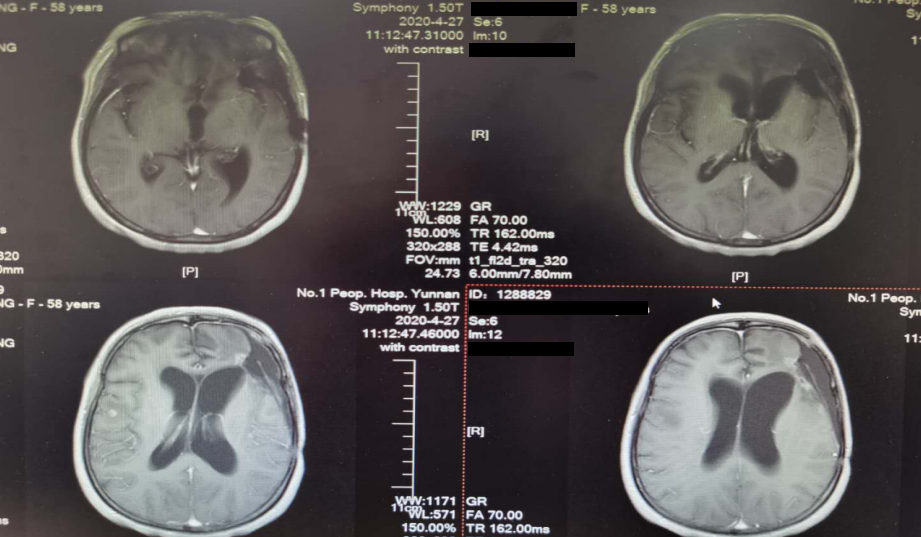

术后半年MRI增强